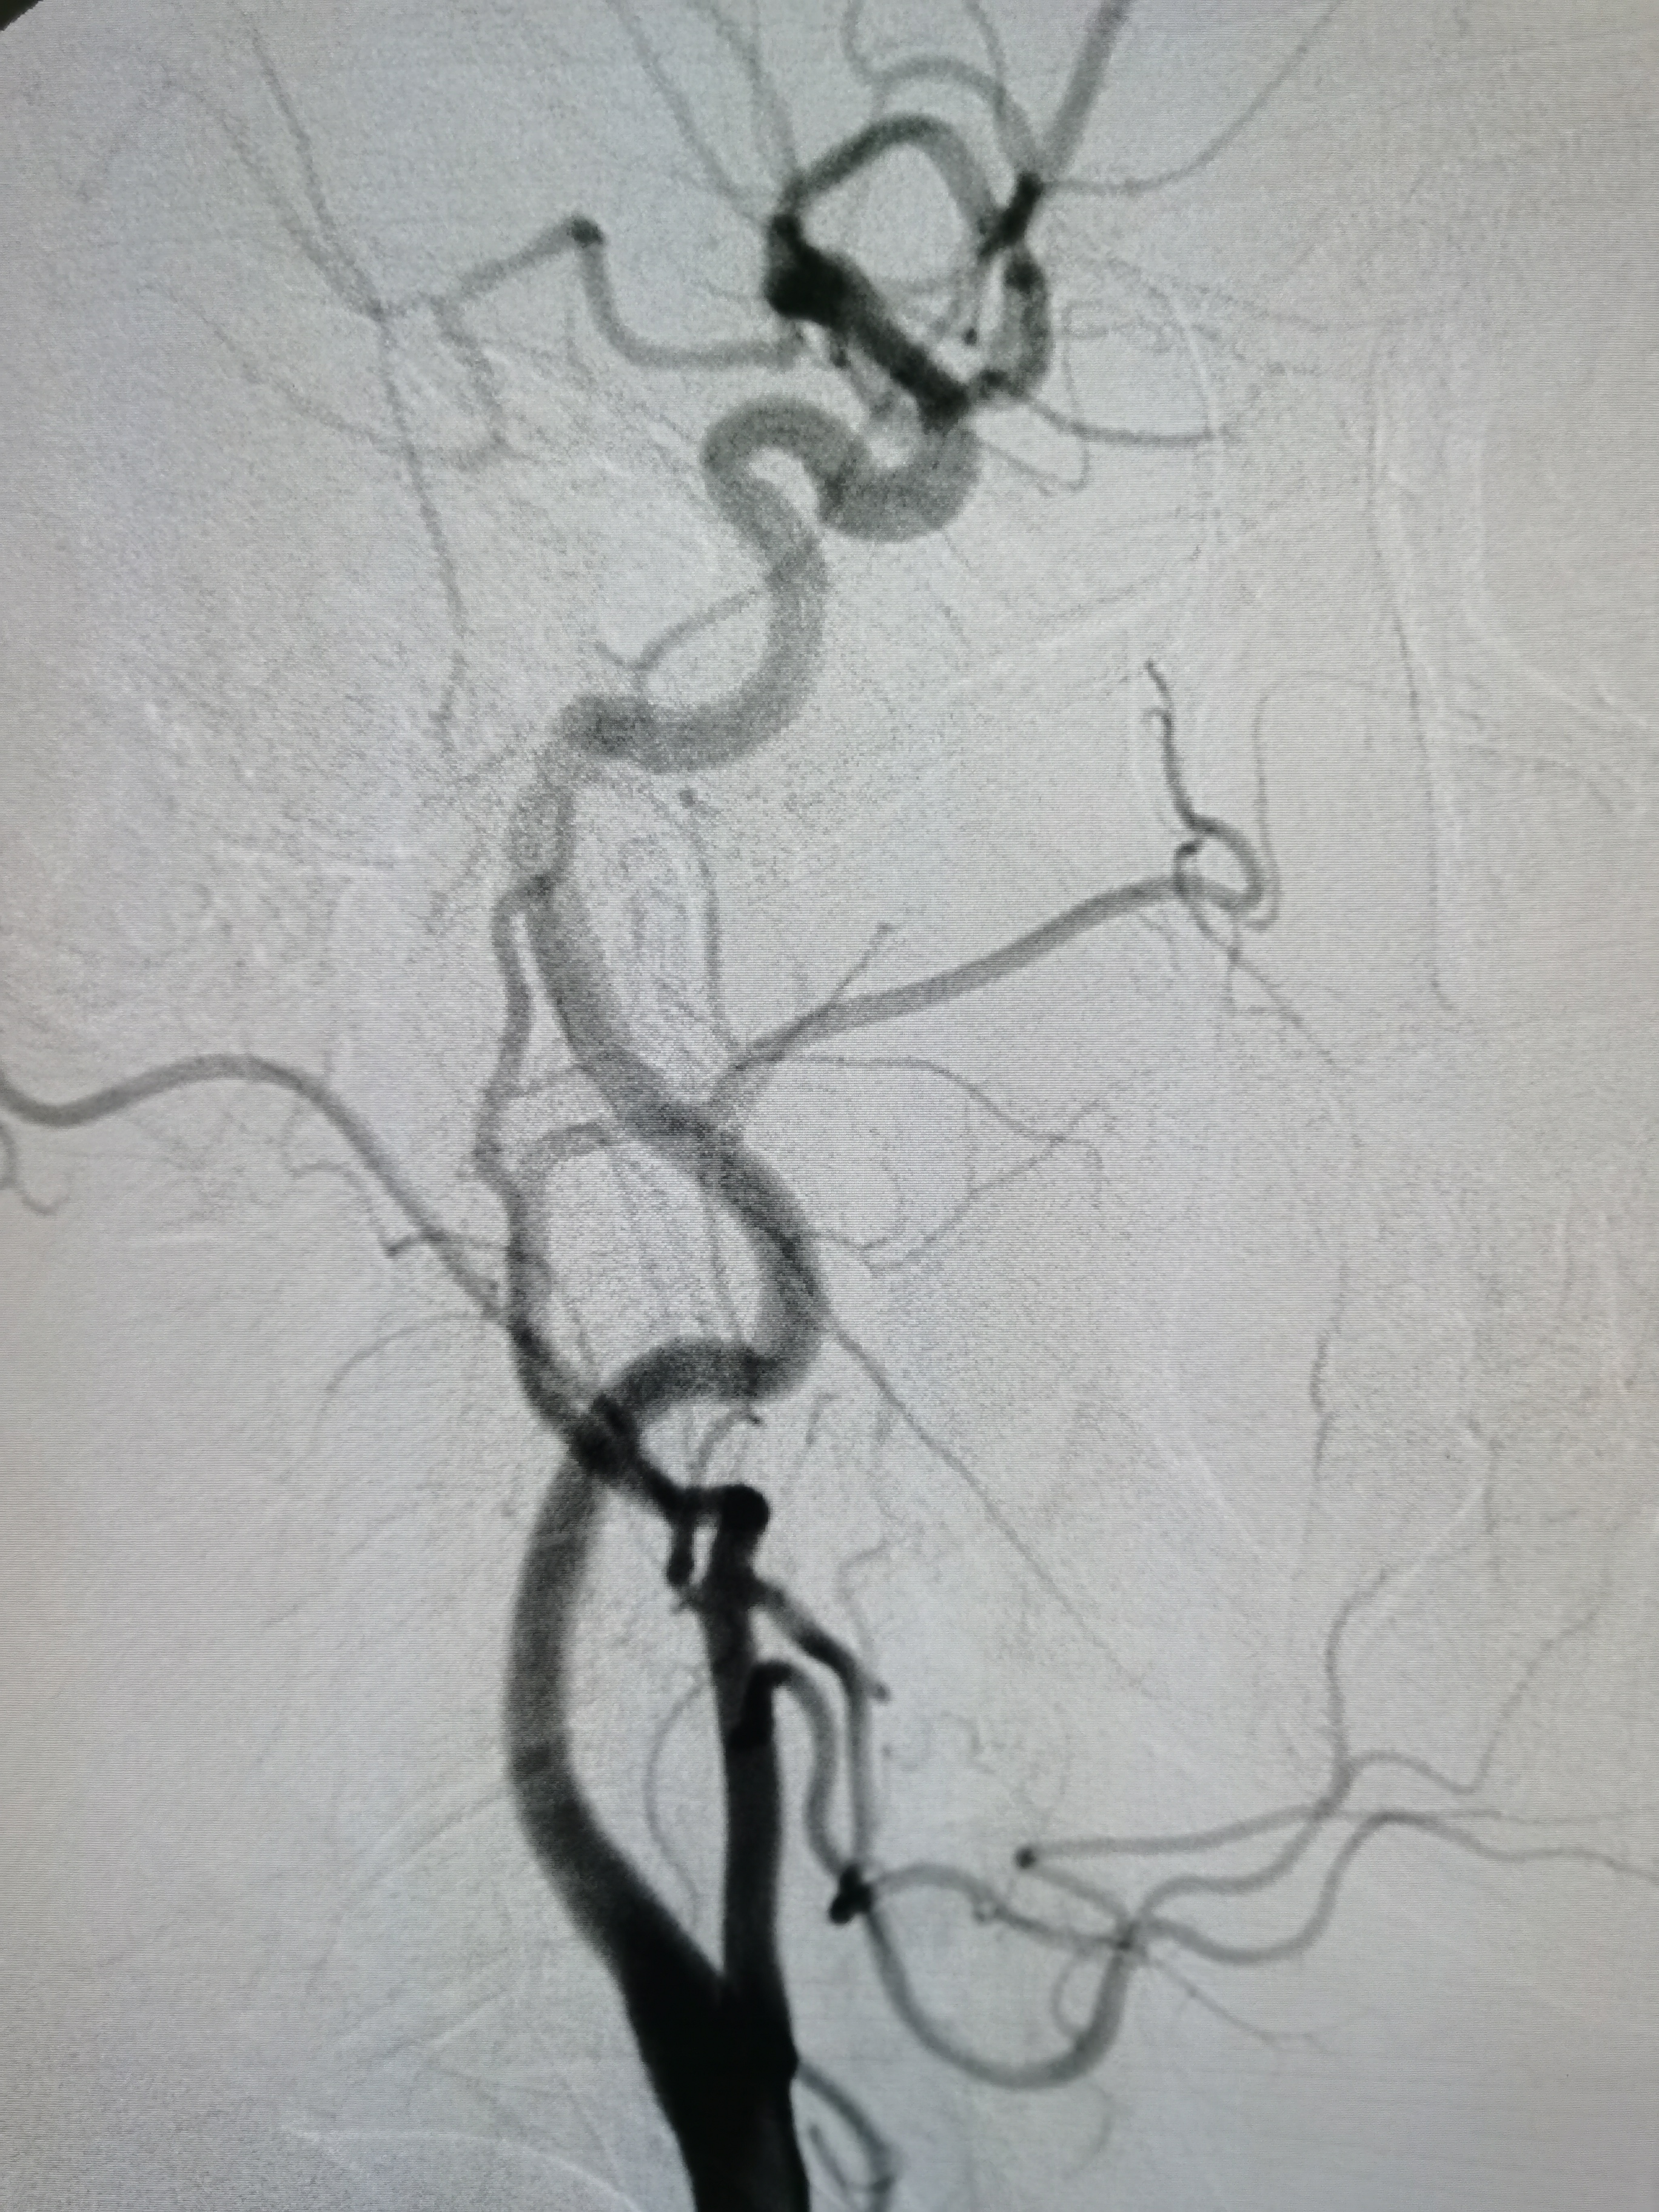

将8F导引导管送至左侧锁骨下动脉近左椎动脉起始部,微导丝顺利通过病变,2.0/20球囊预扩病变。

3、手术过程中,先用小球囊扩张病变,观察血栓情况,及时应用支架全程覆盖血栓及病变部位,成形满意。